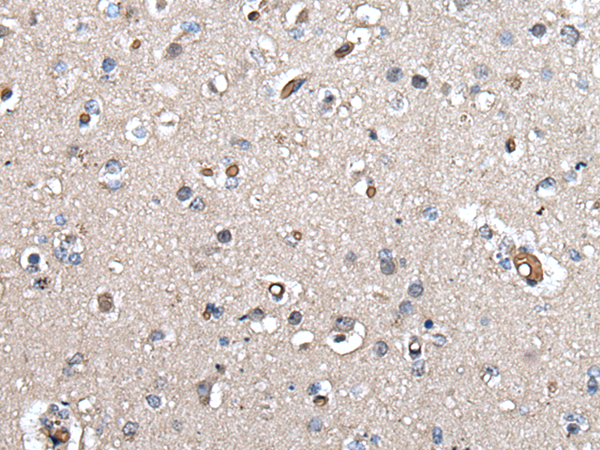

IHC positive control: |

Human brain |

IHC Recommend dilution: |

30-150 |